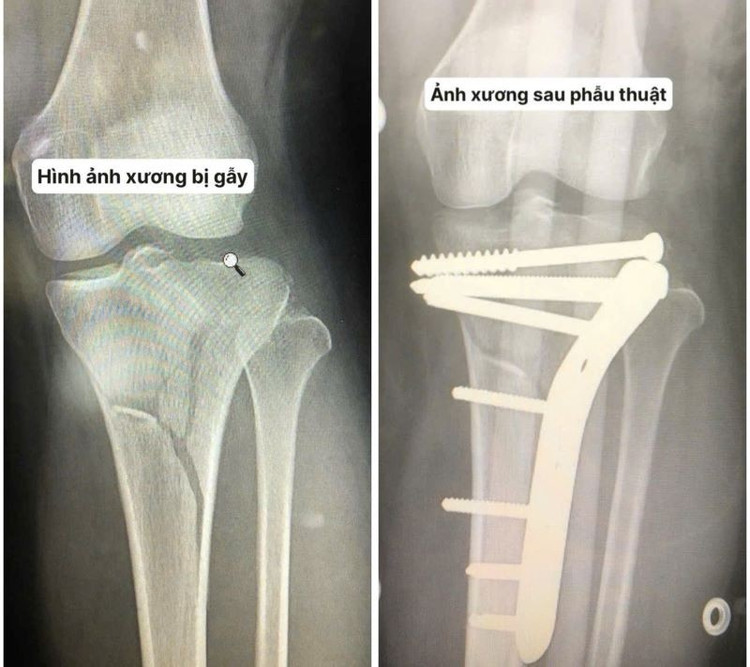

Ngày 17/7, Trung tâm Y tế Quảng Yên (Quảng Ninh) cho biết, Trung tâm đã thực hiện thành công ca phẫu thuật cấp cứu điều trị gãy kín mâm chày trái type VI theo phân loại Schatzker, kèm tổn thương dây chằng chéo trước – một chấn thương nặng nề, phức tạp vùng khớp gối.

Bệnh nhân nữ, 28 tuổi, nhập viện trong tình trạng tỉnh táo, huyết động ổn định, sau tai nạn xe máy tự ngã. Bệnh nhân đau dữ dội, vận động hạn chế gối trái. Khám lâm sàng ghi nhận sưng nề khớp gối, đau đoạn 1/3 trên cẳng chân trái. X-quang cho thấy gãy phức tạp mâm chày trái, siêu âm không có tổn thương mạch.

Trên cơ sở hội chẩn liên khoa, chẩn đoán xác định: gãy kín mâm chày trái type VI theo phân loại Schatzker, kèm tổn thương phần mềm và dây chằng chéo trước. Đây là loại gãy xương nghiêm trọng, thường do lực chấn thương mạnh, có nguy cơ cao gây mất vững khớp và thoái hóa nếu không điều trị kịp thời, đúng kỹ thuật.

Phẫu thuật viên tiến hành rạch da mặt ngoài đầu trên xương chày, bóc tách mô chính xác, đặt lại các mảnh xương đúng trục giải phẫu. Hệ thống nẹp vít chuyên dụng gồm 1 nẹp và 7 vít được sử dụng nhằm đảm bảo sự vững chắc trong giai đoạn liền xương.